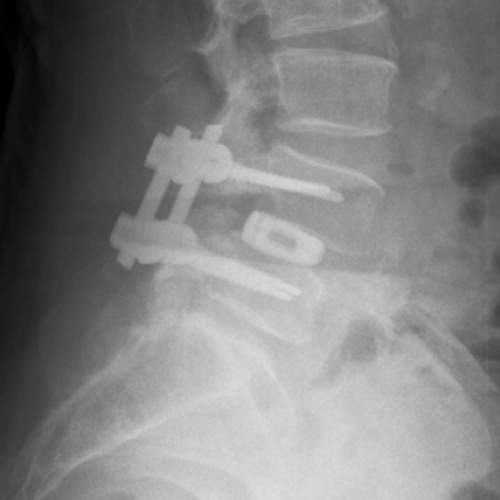

Radiografie din incidenţa laterală ce demonstrează spondilolisteza L4-L5 la o pacienta în vârstă de 54 ani